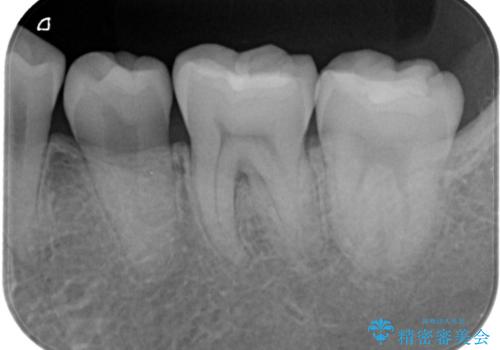

- 昔保険で治療した詰め物の形をずっと気にされていた患者様です。また下の歯なのでお口を開けると見えてしまうことを気にされていました。白く丈夫な被せ物を奥歯に入れたいと希望されたため、セラミックインレーにて治療いたしました。

保険でよく使用されるコンポジットレジンが詰めてありました。時間が経つと劣化しやすい材質なため全て取り除き、形を整えてセラミックインレーを被せました。キレイな歯の形を手に入れることができ、ご満足いただけました。